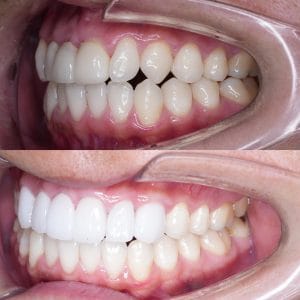

Case033

前歯が虫歯なのと、保険のプラスチックで大きく治療されていて色が悪いこと、歯並びが出っ歯気味であることを気にしてセラミックにしたいという主訴で来院された患者様です。

虫歯が大きかったところは神経治療をきちんと行い、

初診時を含めてトータル4回のご来院で完了です。

今回は前歯を下げる、歯列を整える、白すぎず自然に綺麗に見える色というご希望に沿って治療しました。

ご興味のある方はいつでもご相談ください。

担当 理事長 佐藤 悠野